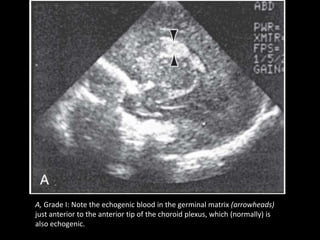

A, Grade I: Note the echogenic blood in the germinal matrix (arrowheads)

just anterior to the anterior tip of the choroid plexus, which (normally) is

also echogenic.

A, Grade I:Note the echogenic blood in the germinal matrix (arrowheads) just anterior to the anterior tip of the choroid plexus, which (normally) is also echogenic.